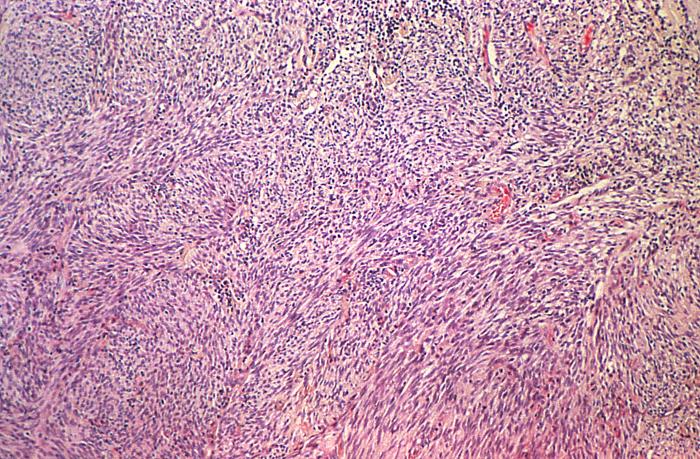

This photomicrograph of a human skin biopsy specimen, revealed the presence of histopathologic changes indicative of a case of Kaposi’s sarcoma (KS). The dermis contained a dense cellular infiltrate, and narrow slit-like vascular spaces that are characteristic in these KS lesions.